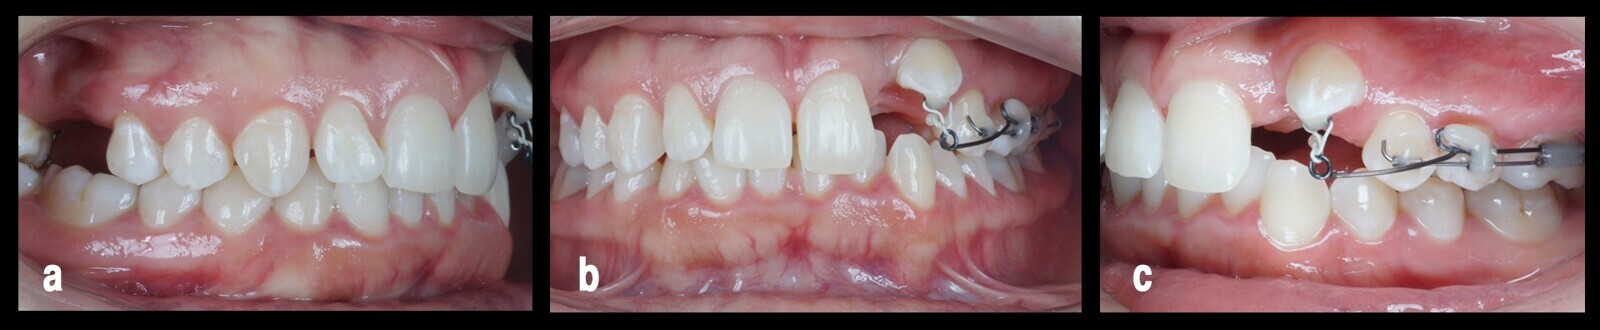

Para disminuir el trauma oclusal sobre los incisivos superiores se suele usar dispositivos tipo bite turbo o topes cementados sobre los dientes superiores caninos o centrales en la superficie palatina, Pero debido a la inadecuada nivelación de los caninos, no era ideal para dichos topes y colocarlos sobre los incisivos aumentaría la carga oclusal. Por esta razón, se decide usar un plano de mordida anterior removible con diente temporal a nivel del 22 para mejorar la estética del sector anterior (Fig. 4).

Figura 4. Fase de nivelación, vista desde tres perspectivas distintas (a, b, c), donde se usó un plano de mordida anterior removible con diente temporal a nivel del 22 (d) para mejorar la estética del sector anterior.